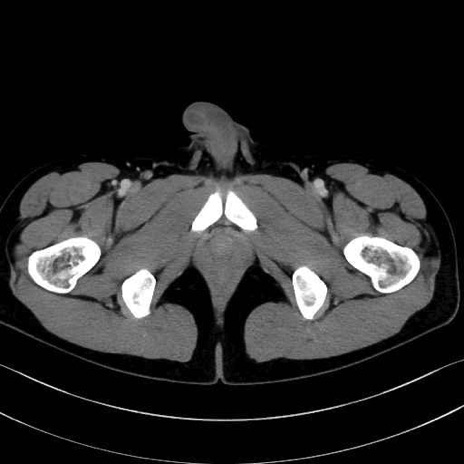

大内転筋・小内転筋 (Adductor magnus / Adductor minimus)